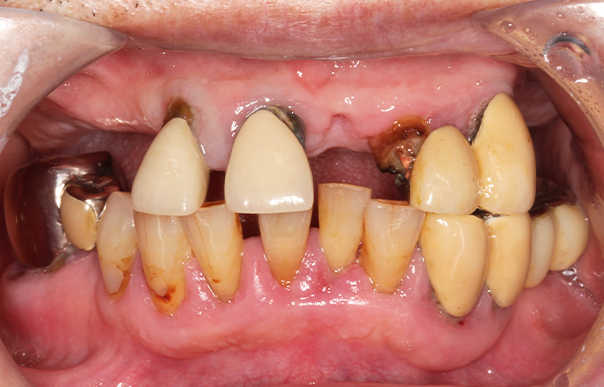

旅行や食事を楽しめるように歯を治したい 【オールオン4・オールオン6】